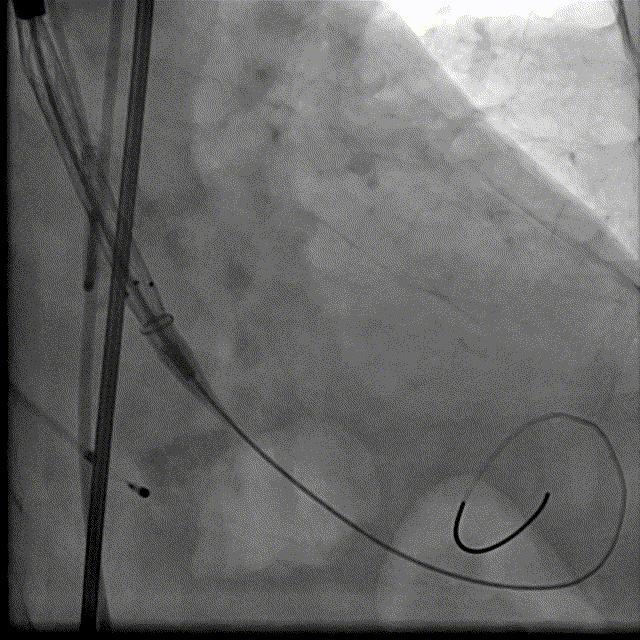

瓣膜释放DSA

瓣膜最终形态